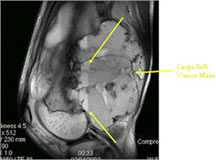

- MRI and CT are also useful for demonstrating the local extent of the tumor and any soft tissue mass

- CT also useful for demonstrating scant osteoid production